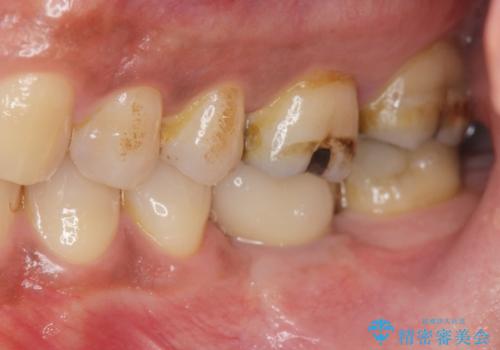

失った奥歯をインプラントで機能回復

- 失った歯の機能回復を希望され来院されました。

取り外しの必要な入れ歯、隣の歯を削る必要のあるブリッジに心理的抵抗があり、インプラントを用いて咬合機能を回復していくこととなりました。